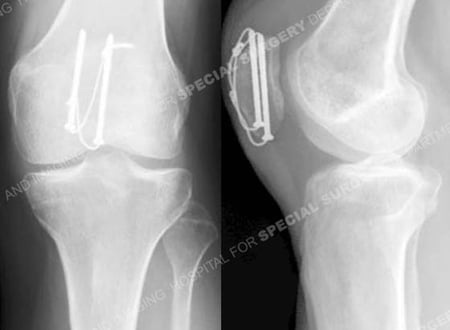

Anteroposterior and lateral radiographs 13 months following fracture surgery illustrating a healed patella fracture in excellent alignment.